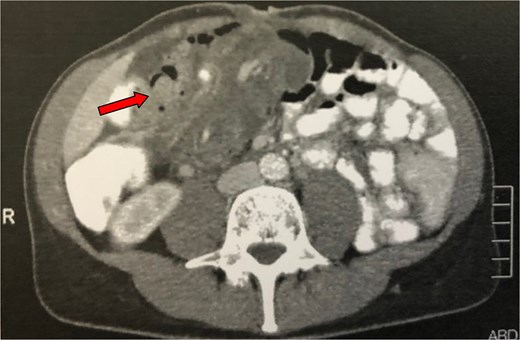

This was later confirmed through a CT scan which depicted an abdominal “mass” with intestinal loops forming a multilayer concentric ring, extending from the ileocolic valve to the left upper abdomen, indicating an ileocolic intussusception (Fig. 3). Emergency surgery was performed, which further confirmed the CT findings by revealing an ileocolic intussusception of a long, ~40 cm segment of small bowel reaching the left colic flexure (Fig. 4). The decision was made to carefully realign the small intestine to minimize the extent of resection. After reduction, a palpable tumor was found in the caecum, identified as the cause of the intussusception. A small enterotomy of the ascending colon allowed direct visualization of the tumour, which appeared macroscopically suspicious for malignancy; therefore, a right colectomy with complete mesocolic excision and a hand-sewn side-to-side ileotransverse anastomosis was performed. Histological examination revealed a villous adenoma measuring 3.5 cm in diameter, located at the base of the appendix vermiformis, with mostly low-grade epithelial dysplasia and a few areas of high-grade dysplasia. The postoperative course was uneventful, and the patient was discharged on the sixth postoperative day.

Abdominal CT of the patient (second case) showing an abdominal ‘mass’ (arrow), consisting of intestinal loops forming a multilayer concentric ring, expanding from the ileocolic valve till the left upper abdomen and suggesting an ileocolic intussusception.